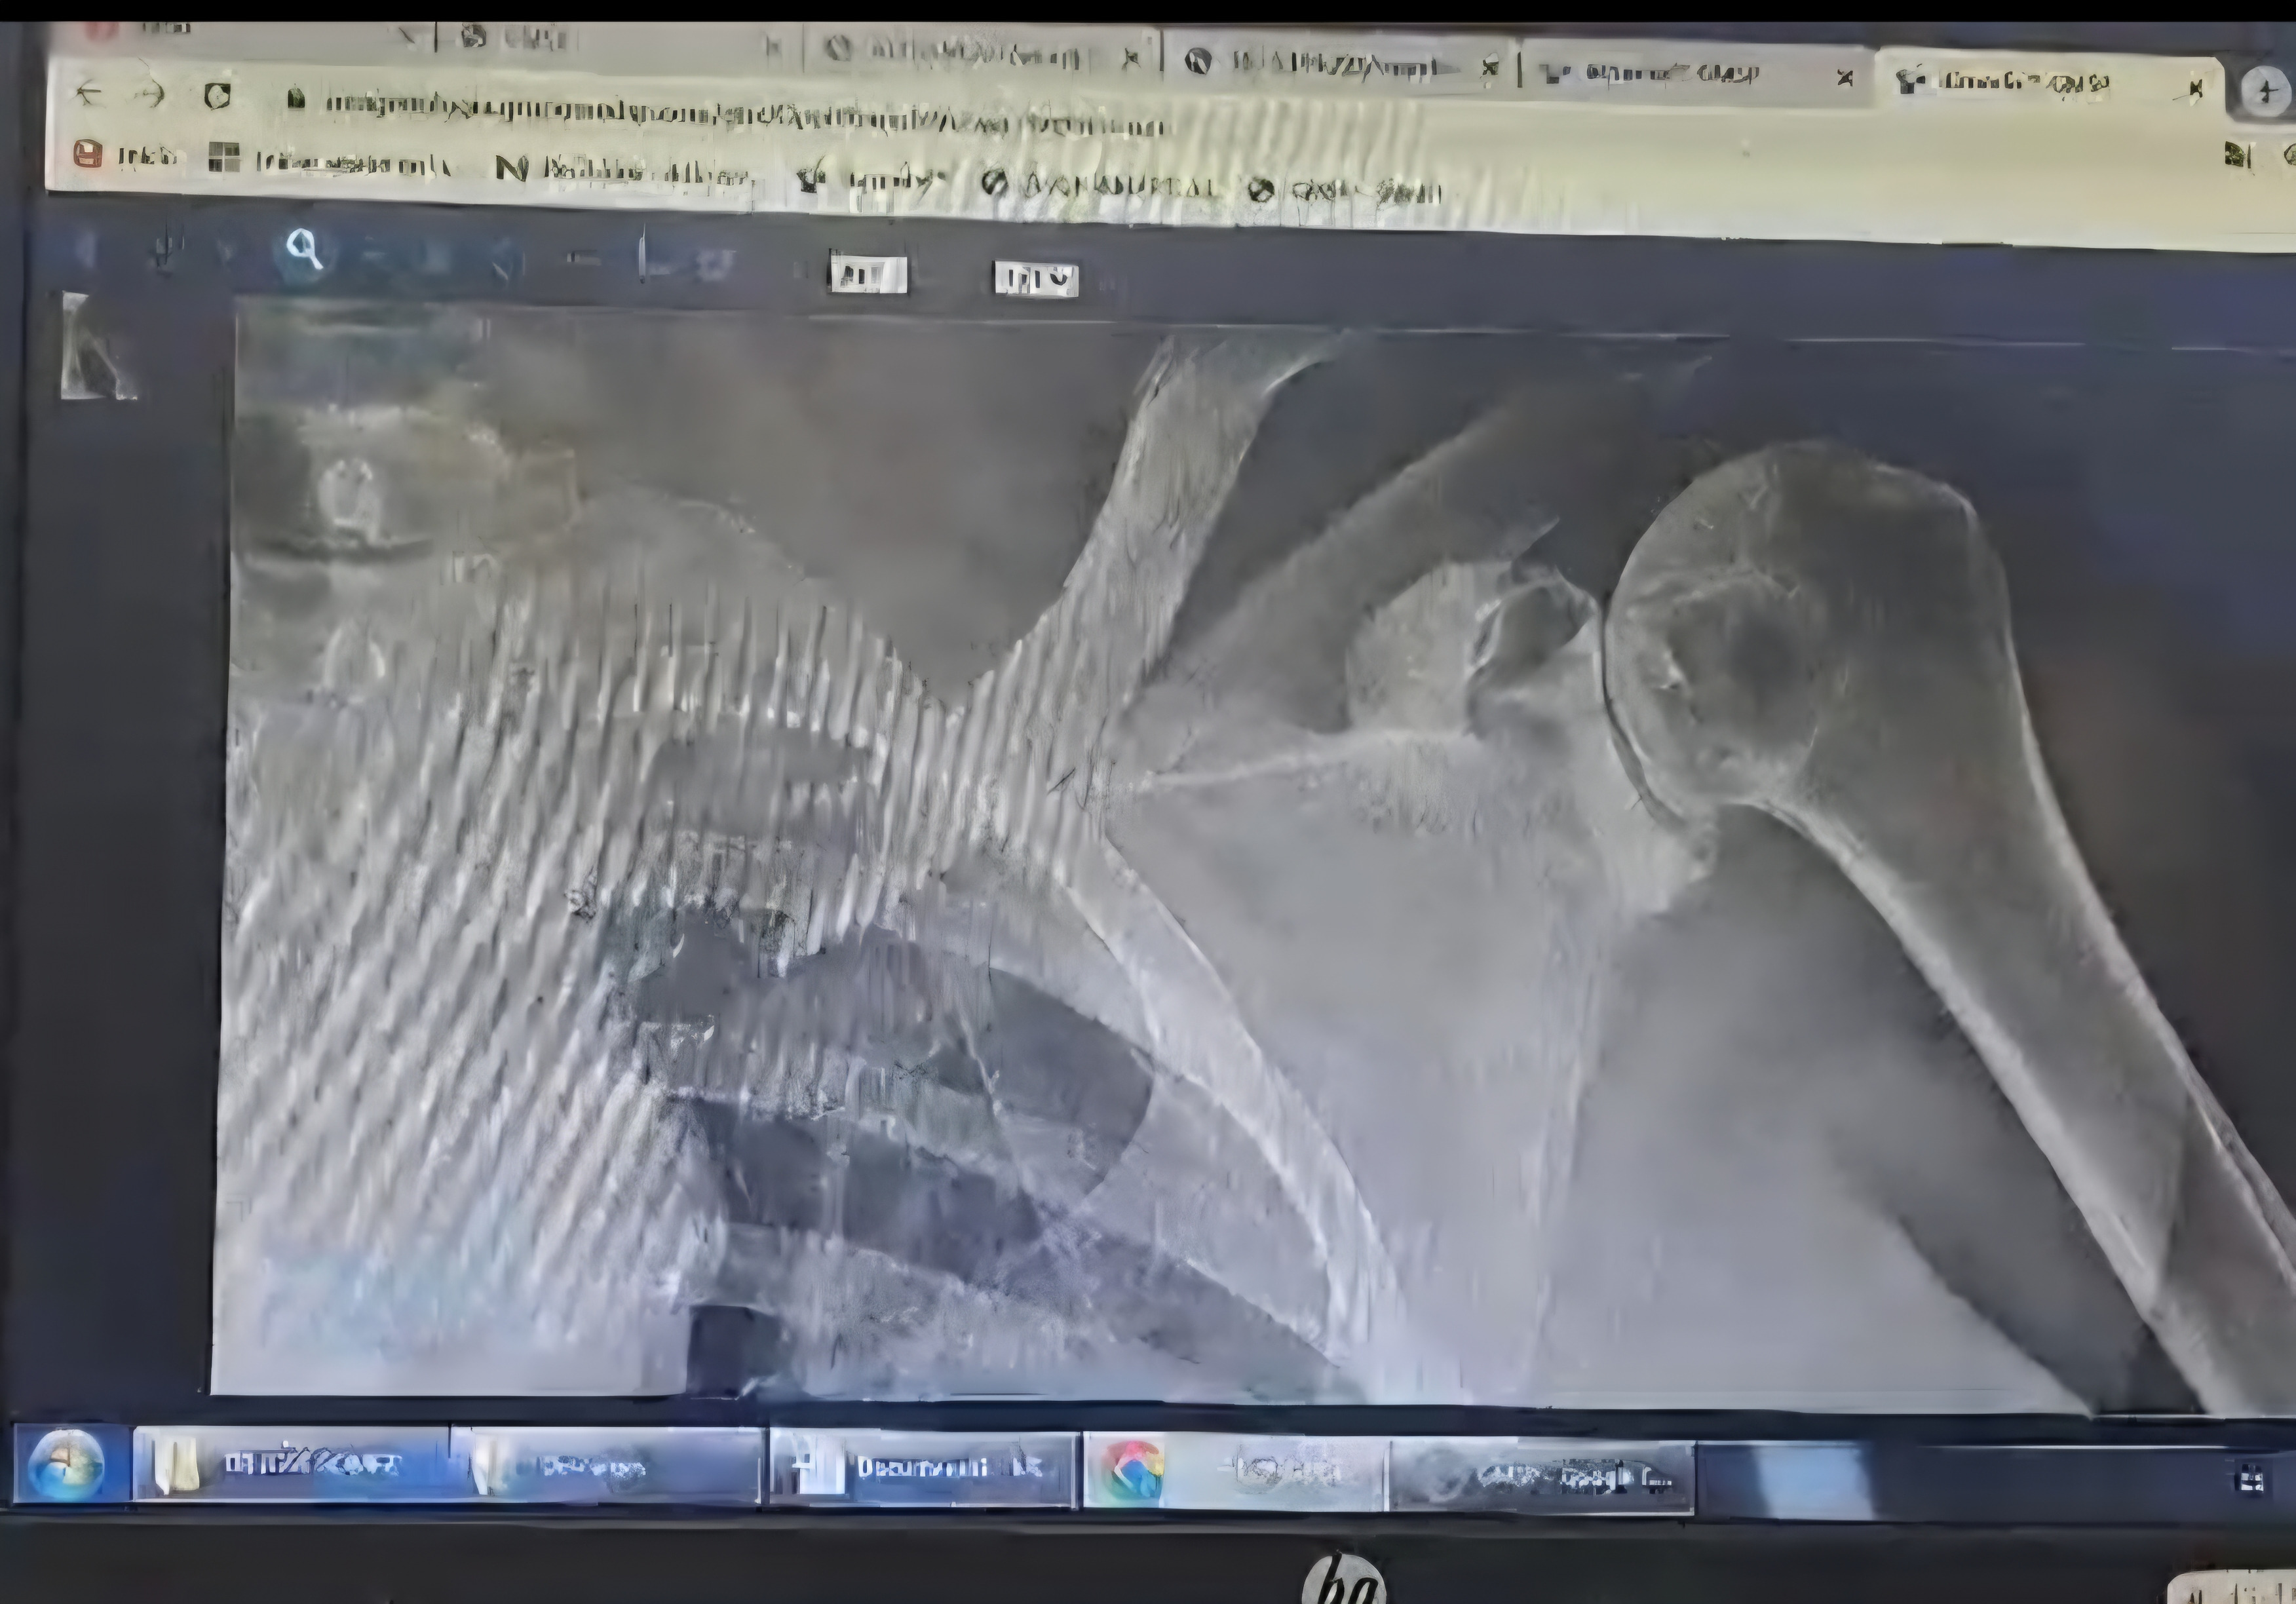

On Saturday, December 12th, my mother, Silvia Tucker de Rivera, was hit by a car while crossing an street on her way back to her home. She was immediately taken to the Santa Paula Medical Group in Caracas and hospitalized. She has multiple fractures, including a broken collarbone, three ribs, pelvis, and knee. She will undergo surgery to correct these fractures and will then face a long and undoubtedly expensive recovery, requiring rehabilitation and 24/7 care for quite some time.

El sábado, 12 de diciembre mi mama, Silvia Tucker de Rivera, fue atropellada por un automóvil mientras cruzaba un calle para regresar a su casa y enseguida fue trasladada y hospitalizada en el Grupo Medico Santa Paula en Caracas, tiene múltiples fracturas, entre ellas: clavícula, tres costillas, pelvis y rodilla, motivo por el cual será sometida a una operación para corregir sus fracturas y luego enfrentará una recuperación larga y claramente costosa por lo que necesitará rehabilitación y ayuda 24/7 durante un buen tiempo.